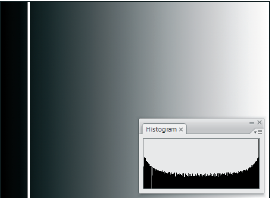

- OpenCV Python Program to analyze an image using Histogram

- Обработка изображений в цифровой фотографии. Анализ гистограмм

- Гистограмма изображения и выравнивание гистограммы

- Чтение гистограммы на примере цветной фотографии

- Что такое гистограмма?

- Гистограммы камер: цвет и контраст

- Гистограмма (фотография)